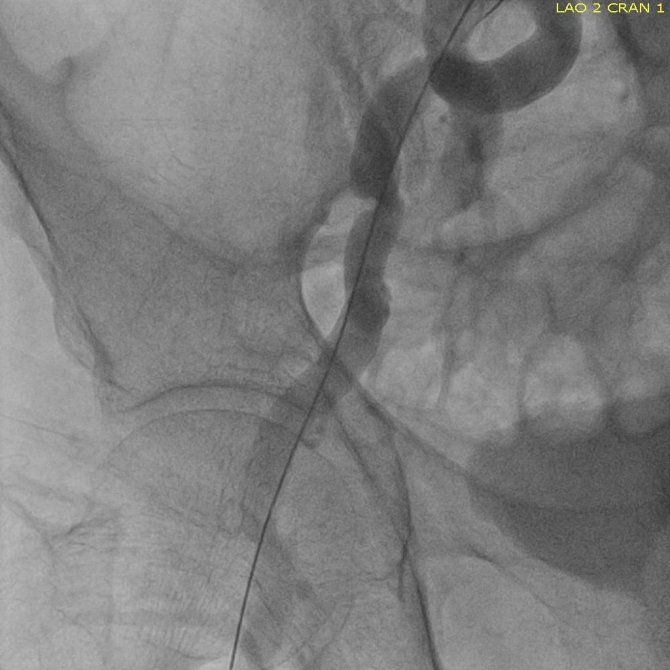

Sekiz yıl önce geçirdiği operasyonla aort kapak operasyonu değiştirilmiş bir hastaya TAVİ yöntemi ile müdahale ettiklerini söyleyen Doç. Dr. Servet Altay, "Hastamız 72 yaşında. 8 yıl önce aort kapağı biyolojik kapakla değiştiriliyor. Bu kapaklarında 10 yıllık bir ömürleri var. Hastamız bize geldiğinde ileri derecede nefes darlığı çekiyordu. Ayrıca aort kapağı değişen birinde ikinci operasyonun riski daha yüksek oluyor. Ekip olarak bu hastaya ne yapacağımızı düşündük. Daha önce bu bölgede yapılmayan bir işlemi yapmaya karar verdik. Türkiye'de de çok yaygın olduğunu düşünmüyoruz. Bozulmuş biyolojik kapağın yerine TAVİ dediğimiz yöntemle yeni bir kapak ekledik ve hastamızı sağlığına kavuşturmuş olduk. Bundan sonra da bu vakalara devam edeceğiz. Hasta günlük ihtiyaçlarını bile karşılamayacak durumdayken bu operasyonla kısa zamanda tamamen sağlığına kavuşmuş oldu. Açık bir ameliyat olmadığı için hastamız hiçbir şey hissetmedi. Yoğun bakımda da kısa bir yatıştan sonra direkt servise aldık. Bizim ve hasta için konforlu bir işlem oldu" dedi.

Yenilikçi bir yaklaşımla müdahalede bulundukları hastanın da benzer bir hikâyesi olduğunu söyleyen Dr. Öğr. Üyesi Uğur Özkan, "Hastamızın durumunu kliniğimizde ve konseyimizde değerlendirdik ve TAVİ kararı aldık. Hastaya işlemi gerçekleştirdikten sonra 24 saatten kısa bir süre yoğun bakım ve 48 saatten kısa servis yatışı oldu. Hasta açısından hem konforlu hem yoğun kan sulandırıcı kullanımı gerektirmeyen, günlük hayatına çok çabuk bir şekilde dönebileceği bir işlem oldu. Hastada çok çabuk ve güzel bir yanıt aldık. Üç gün önce nefes alamayan hastamız bugün yürüyerek servis içinde dolaşmaya başladı" şeklinde konuştu.